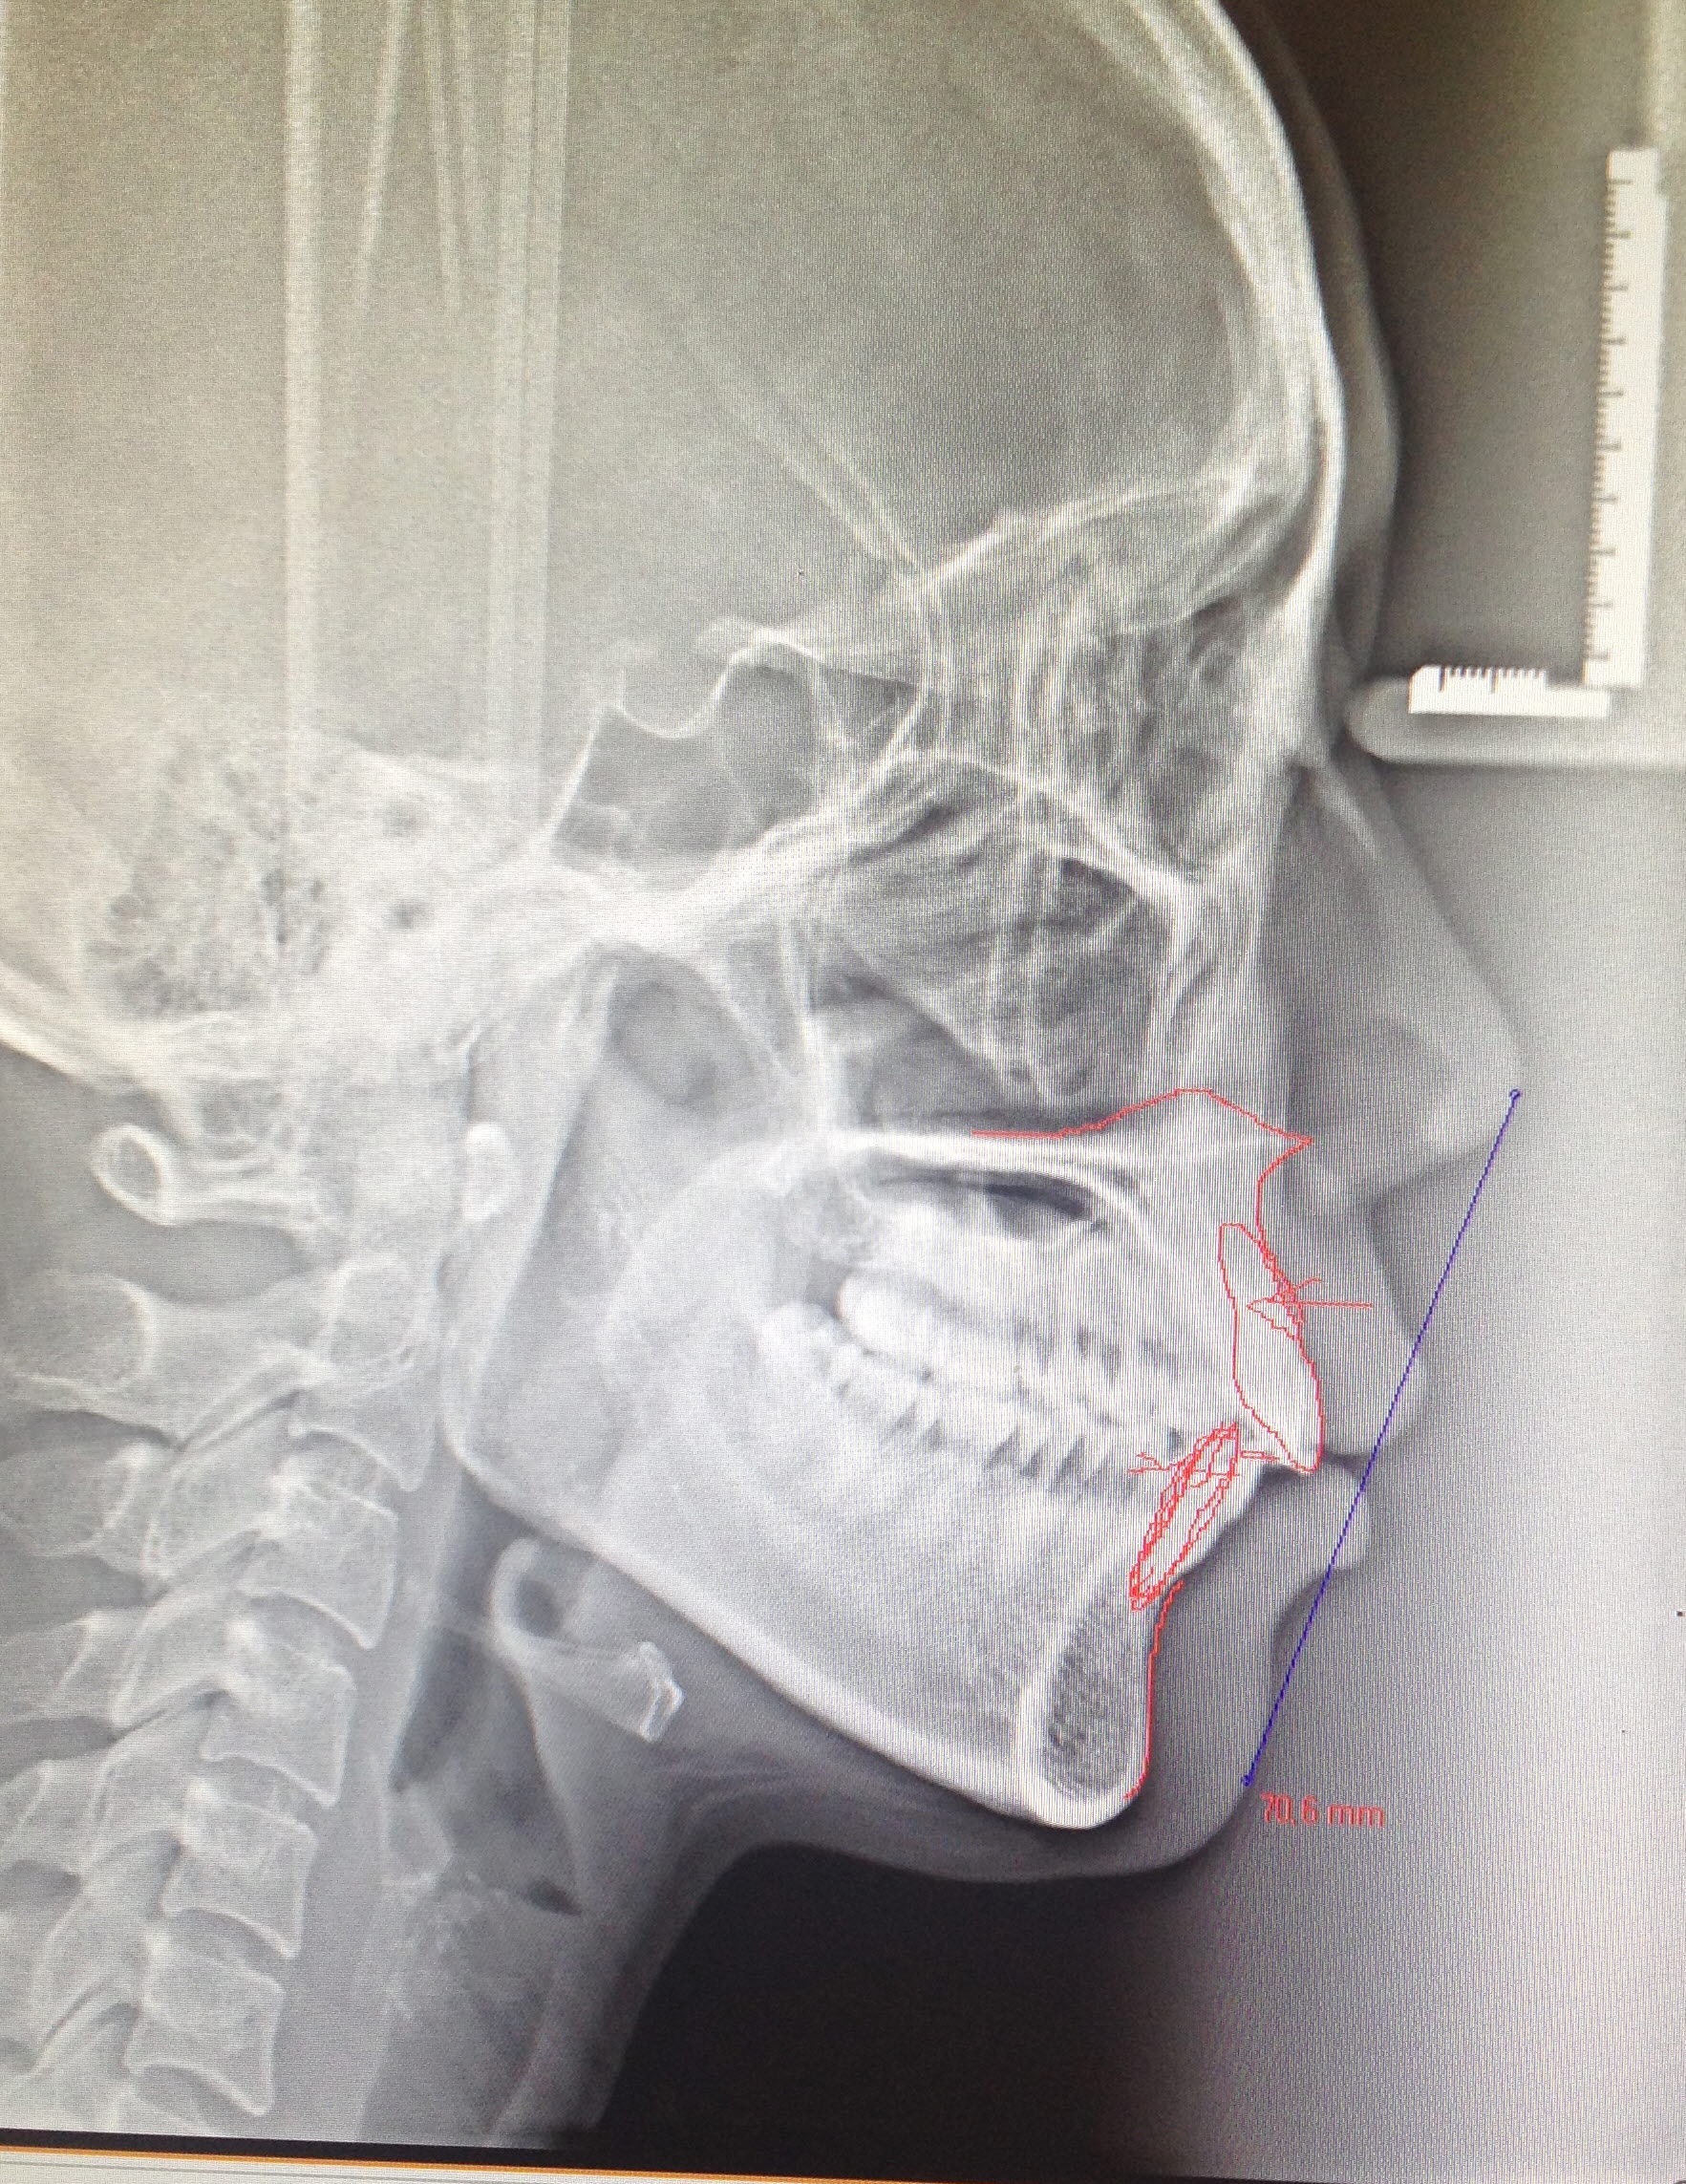

교정 생각 중인 돌출입인입니다.

어제 치과에서 상담을 했는데, 발치와 비발치 중 어떤걸 선택해야할지 고민이에요.ㅠㅠ

보시다시피 잇몸과 치아가 약간 돌출된 상태이고, 치열이 살짝 틀어져있는데요,

네... 사진 잘 보았습니다. 님의 옆모습을 보면 주치의 샘 말데로 님의 경우는 비발치로 진행을 하여도 될 것 같습니다. 발치를 하고 진행할 만큼의 돌출입은 아니듯...^^ 바로 발치하는 것보다는 일단 비발치로 진행을 해 보고 나중에 다시 주치의샘과 상의하는 것이 좋을 것 같습니다.